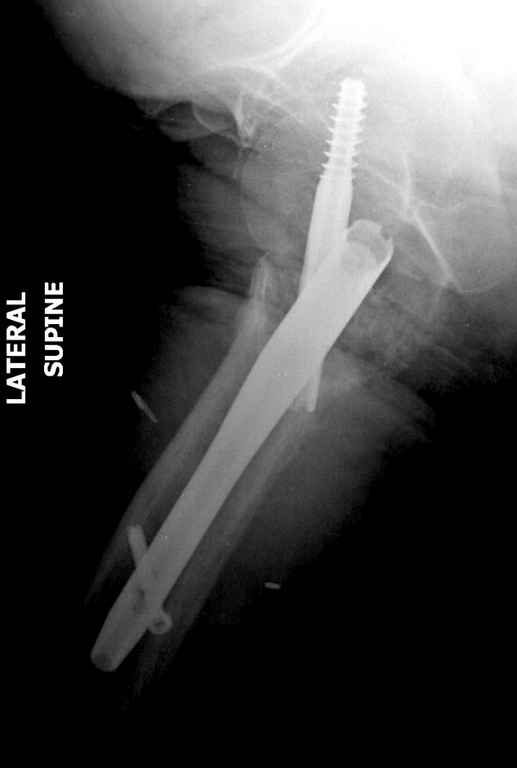

Вашему вниманию представляется похожий случай, пациентке 70, осложнился в течение одного месяца после операции. Ревизия с заменой сустава, кабельная фиксация на трохантер. При установке в дистальном диафизе обнаружен тонкий кортикальный слой и сделана профилактика от возможного перелома аллографтом.